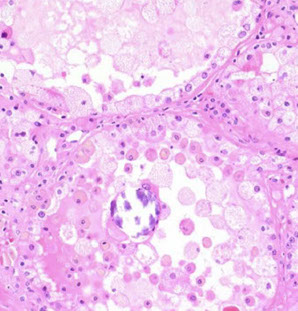

Hemolytic Uremic Syndrome

Endothelial injury results in acute renal failure, caused by systemic microthrombi formation, plt consumption and hemolytic anemia that can result in local necrosis

- MCC ARF in kiddos

- triad: ARF, tbcpenia, MAHA

- can have neuro sx, coagulopathy (similar to TTP)

- usually follows URTI or flu-like illness, can come from fast food hamburgers or spinach / lettuce

Typical HUS manifests as hemorrhagic diarrhea, rapidly progressive renal failure, assoc c O157:H7 cytotoxic E. coli infx

Atypical HUS lacks diarrhea, usually 2/2 complement dysregulation c persistence of complement-mediated microvascular injury

- MC in adults, rarely assoc c ADAMTS13

LM: endothelial injury c edema, sometimes microtrhrombi c fibrinoid necrosis, usually affecting glomeruli; arterial fibrinoid necrosis and thrombosis can be seen, can have glomerular crescents or renal cortical necrosis in severe cases

IF and EM: non-specific; has features of endothelial injury and fibrin staining of microthrombi

Px: kiddos c typical HUS usually recover; atypical HUS (w/o diahhrea) has worse long-term prognosis and can relapse and progress (up to 1/2 mortality)